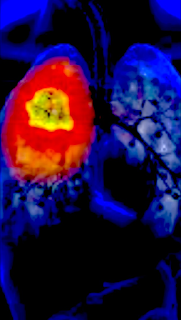

LUNG CANCER. WARNING SYMPTOMS.

Compared to the other types of cancer, lung cancer is the deadliest type worldwide with the highest number of casualties.

• CT or scan.